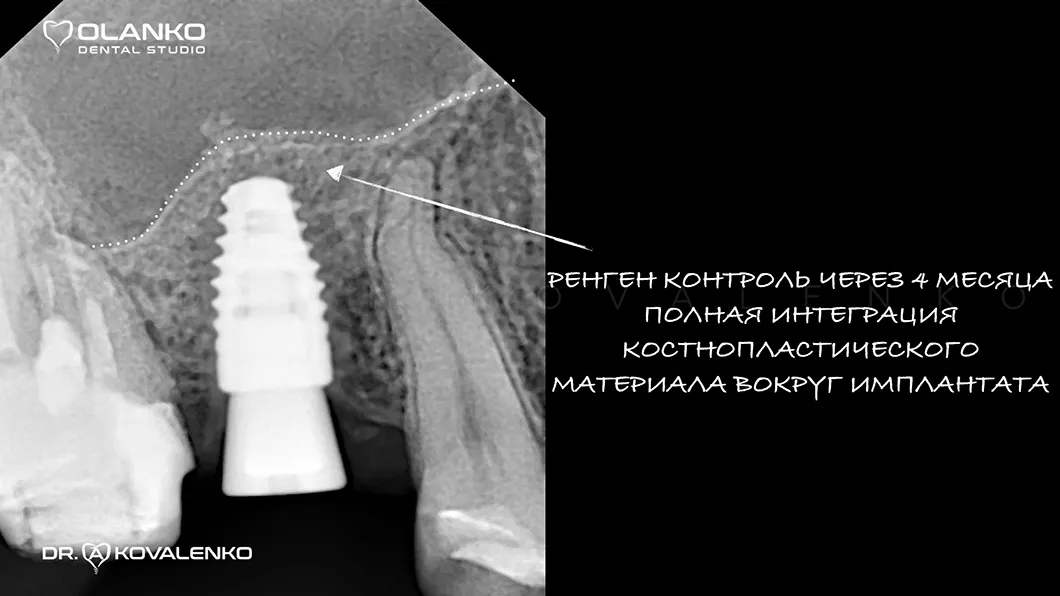

Кісткова пластика щелепи інтеграція матеріалу з костною тканиною Оланко Бровари Київ